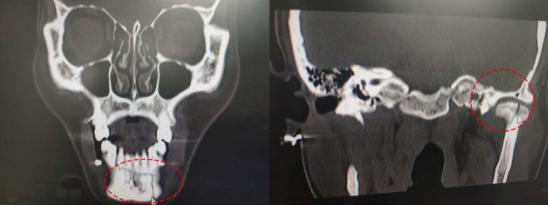

(颌间牵引示意图,红圈为螺钉固定位置)

“颌间牵引是在局麻下,上下颌骨区适当位置植入种植钉,通过橡皮圈牵引复位固定。使下颌骨固定于上颌骨并得以持续的复位调节,使发生骨折并移位的骨组织怀有恢复正中咬合关系或原有的咬合关系。由于种植牵引钉的固定并不依赖牙齿,因而比牙周夹板有着更广阔的适应证,单纯上颌骨折、单纯下颌骨折、上下颌骨联合骨折、牙槽骨骨折、髁突骨折,单发骨折、多发骨折,新鲜骨折、陈旧性骨折等均可采用。”徐主任介绍,该手术平均操作时间约为10分钟左右,在门诊局部麻醉下就可以完成。而且,牵引钉对患者口腔黏膜的刺激少,患者感觉较为舒适,利于患者尽早恢复咀嚼功能。